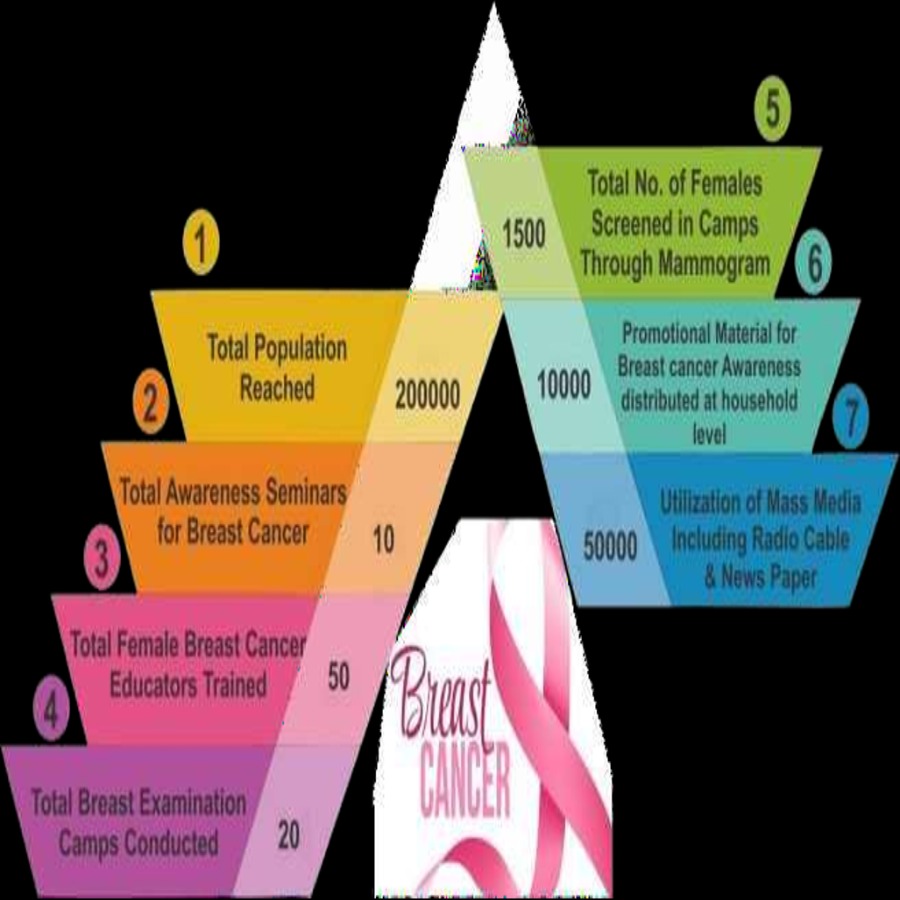

Health